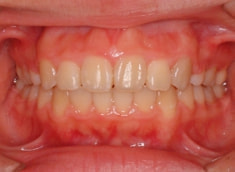

上顎前突ケース

治療法:表の矯正(T21ブラケット)

治療後(1年2ヶ月後)